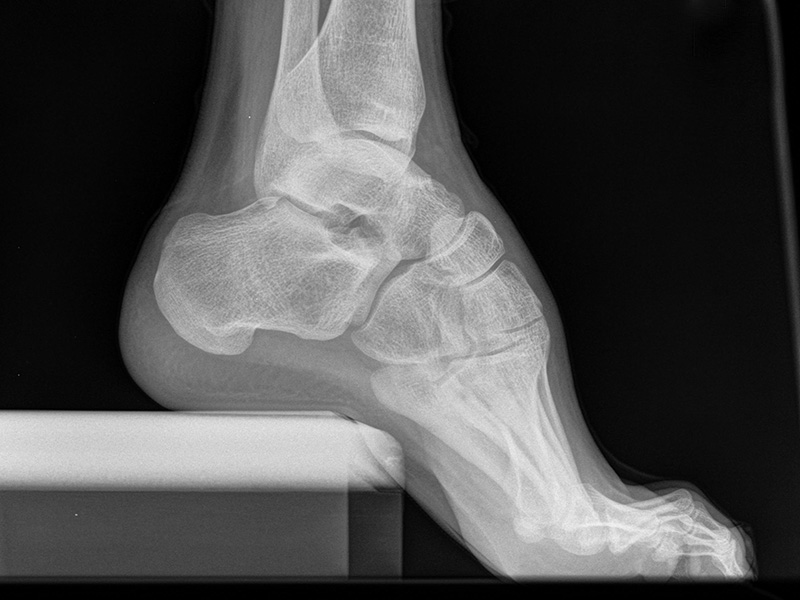

Fuß seitlich mit Belastung

Positionierung:

• Der Patient steht auf beiden Füßen mit gleichmäßiger Lastverteilung.

• Der zur Röntgen der Fuß wird längs des Films positioniert.

• Die Kassette steht senkrecht zum Boden, medial dem Fuß anliegend.

• Der Zentralstrahl wird von lateral nach medial zentriert auf das Kalkaneokuboidalgelenk knapp cranial der Os metatarsale V Basis ausgerichtet.

• Die Röntgenröhre steht 0° horizontal.

Kennzeichen des Röntgenbildes:

• Standardabbildung des Fußes zusammen mit der belasteten d.-p. Aufnahme und der unbelasteten 45° Pronationsaufnahme.

• Überblick über die Fußanatomie und Fußstatik.

• Die seitliche Aufnahme liefert Informationen zur Stabilität des Längsgewölbe und zu den Achsen von Talus, Kalkaneus und Metatarsale I.

• Die Aufnahme wird eingesetzt zur Darstellung von freien Gelenkkörpern sowie knöchernen Veränderungen am Achillessehnenansatz oder der Plantarfaszie.